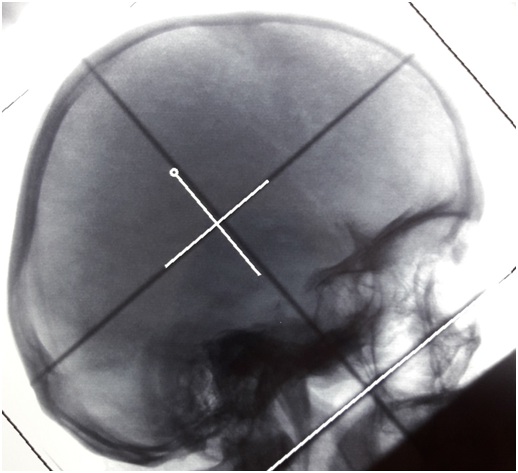

The written informed consent of the patient was obtained and she underwent whole brain and orbital irradiation (3000 cGy in 10 fractions, daily, from Monday to Friday) (Figure 3). At the same time, the patient received desmopressin, with a gradually increasing dosage (initially 60mcg daily and then 120mcg daily), which resulted in controlling symptoms of central diabetes insipidus. Consequently, the patient was treated with immunotherapy and chemotherapy (pertuzumab, trastuzumab, docetaxel for 8 cycles every 3weeks and then continued on with pertuzumab and trastuzumab). Anti-HER’s-2 antibodies, plus the receptor activator of nuclear factor κ B ligand (RANKL) inhibitor (denosumab) is still administering. The patient is still alive, with full control of central diabetes insipidus and with partial remission of the pituitary tumor. Diabetes insipidus may occur in the course of the disease in a patient with metastatic breast cancer. The particularity of our patient, is that the disease appeared with symptoms of diabetes insipidus.

Figure 3 Whole brain - Orbital radiotherapy field.